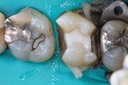

Kris Nip #19 pre-op

Kris Nip #19 amalgam removal